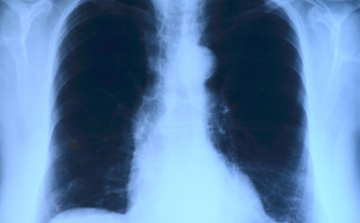

Először találtak élő emberek tüdeje mélyén műanyag mikroszemcséket

Először találtak élő emberek tüdeje mélyén műanyag mikroszemcséket: műtéten átesett 13 páciens közül 11-ben fedezték fel a részecskéket.